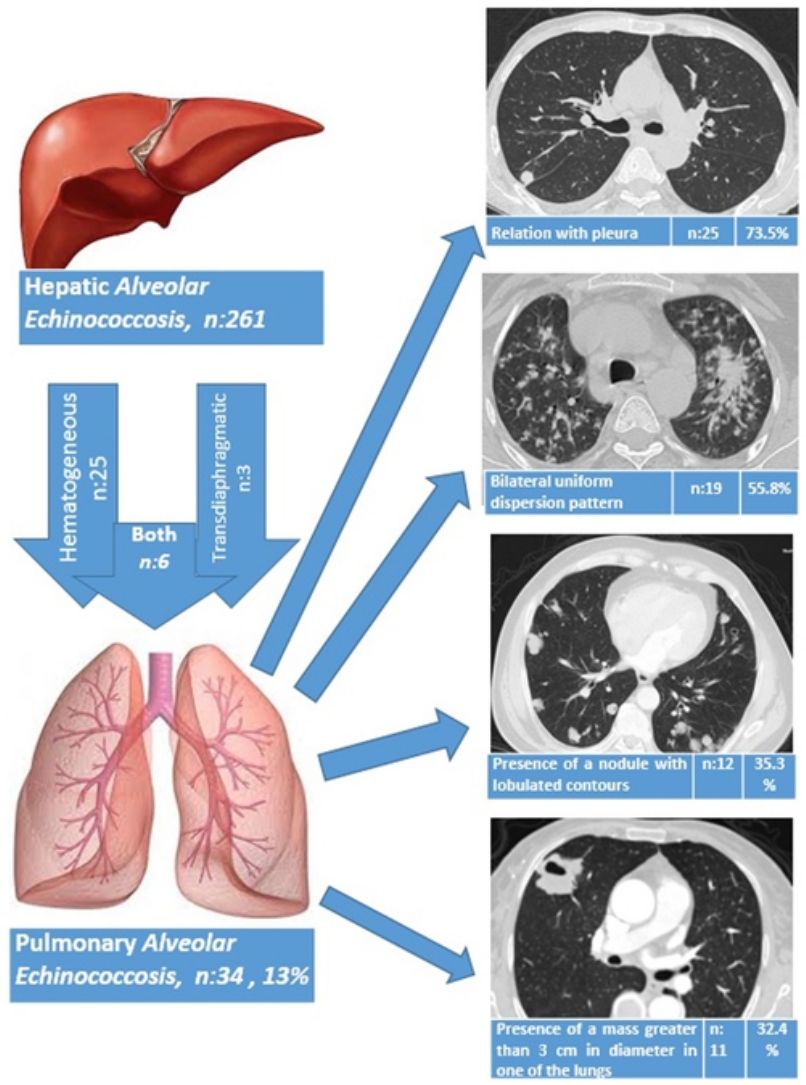

ResultsThe liver was the primary involved organ in all cases. Pulmonary involvement was detected in 13.0% (34/261) of all cases with hepatic alveolar echinococcosis (AE), and three patients (8.8%) had both pulmonary metastasis and brain metastasis. The route of spread to the lungs based on radiological data was hematogeneous in 25 patients (73.5%), transdiaphragmatic in three patients (8.8%) and both hematogeneous and transdiaphragmatic in six patients (17.7%). AE showed bilateral involvement in 19 patients (55.9%), whereas only the right lung was involved in 12 patients (35.3%) and the left lung in three patients (8.8%). Of the patients, five underwent surgery due to PAE and 29 patients received medical therapy with albendazole. A total of three patients died during the follow-up period (2, 5 and 10 years after the diagnosis of PAE), while 31 patients continued with follow-up and treatment for a mean duration of 5.4±3.8 years (1–14 years).

The route of spread to the lungs based on radiological data was hematogeneous in 25 patients (73.5%), transdiaphragmatic in three patients (8.8%) and both hematogeneous and transdiaphragmatic in six patients (17.7%). AE showed bilateral involvement in 19 patients (55.9%), whereas only the right lung was involved in 12 patients (35.3%) and the left lung in three patients (8.8%).

A relationship was identified between the pleura and one or more of the lesions in 25 of the 34 patients diagnosed with PAE (73.5%) (Fig. 1). Following the lesion-pleura relationship, multiple lesions were uniformly scattered throughout the bilateral lung parenchyma in 19 patients (55.8%), seven patients (20.6%) presented with a solitary pulmonary lesion and three patients (8.8%) had multiple unilateral lesions. The diameter of one or more lesions was greater than 3cm in 11 patients (32.4%), only three patients (8.8%) had conglomerated lesions (Fig. 2) and seven patients (20.6%) showed cavitization in some of the lesions. The majority of cavitary mass measured greater than 3cm (Fig. 3). Calcified lesions were recorded in five patients (14.7%), and some of the calcified lesions with lobulated contours had a typical popcorn appearance. Lobulated contours were observed in a significant proportion of non-calcified lesions. Some of the lesions had irregular contours and spicular extensions mimicking malignant processes in five patients (14.7%), while three patients (8.8%) showed multiple micronodular densities with a bilateral uniform dispersion pattern (Fig. 4). The appearance of pulmonary involvement resembled miliary tuberculosis. Parenchymal lesions were accompanied by pleural effusion and parenchymal consolidation in only three patients (8.8%) (Table 1).

Small nodules in the liver and lung parenchyma are asymptomatic, and the disease may be detected incidentally on ultrasound, CT or MRI performed for other reasons. USG and CT reveal central necrosis, calcifications, irregular contours, and heterogeneous and hypodense foci. MRI is superior in the identification of central necrosis, however, this method does not serve well in the differential diagnosis of calcifications and small lesions. Positron emission tomography-computed tomography (PET-CT) is an important method for detecting the extent of the disease in the body and disease recurrence, and in identifying the viability of the parasite. Imaging studies often show findings that are suspicious for carcinoma or sarcoma. The general medical condition of patients with AE is better than those with suspected malignancy, as was the case in the present study.9 The most common pulmonary findings of CT scans of patients were a relationship with the pleura (73.5%), a bilateral uniform dispersion pattern (55.8%), the presence of a lesion with lobulated contours (35.3%) and the presence of a mass measuring greater than 3cm (32.4%). The lesion showed spicular extensions in 14.7% of the patients, mimicking malignancy.